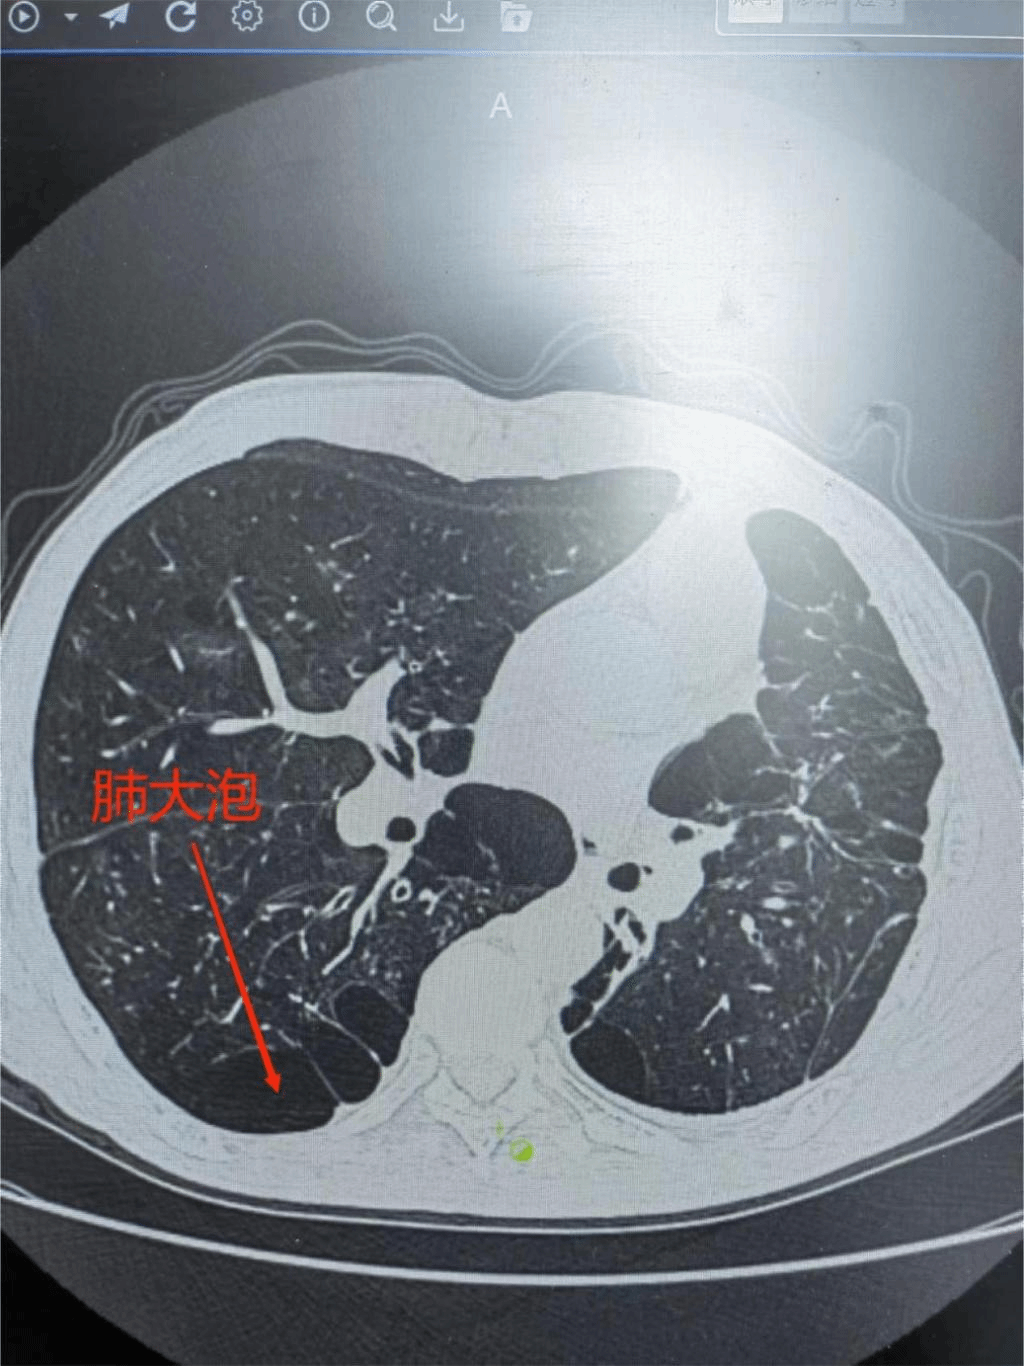

1月29日九江学院第二附属医院呼吸内科付云杰主任团队在胸外科张毅博士、麻醉科李成涛主任的协助下,成功为一例重度慢阻肺患者成功实施经无痛支气管镜双肺EBV活瓣肺减容术,一次性为患者处理了双侧肺大泡。术后患者即可起床活动,饮食照常,完全无痛,胸闷、气喘症状得到明显缓解,效果立杆见影。这是我院第二例支气管镜单项活瓣肺减容术,也是九江地区首例双肺支气管活瓣肺减容术。标志着我院支气管镜介入技术迈入新台阶,将造福更多九江乃至周边区域的患者!

据悉,经支气管镜单向活瓣肺减容术,是一种支气管镜下介入治疗的新技术,放置在支气管内的活瓣,允许分泌物和气体从活瓣远端肺组织排出,但阻止气体进入活瓣远端肺组织,从而使靶肺组织逐渐萎陷不张,达到减容的目的。该新技术具有疗效显著、创伤小、病人耐受好、术后康复快、并发症少和住院时间短等优势。经支气管镜单向活瓣肺减容术的成功开展,为广大不均质肺气肿表型、叶间裂完整的慢性阻塞性肺疾病患者带来了新的选择。